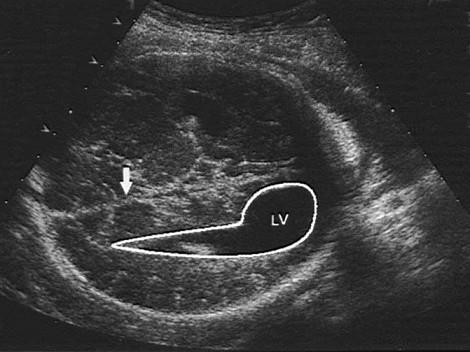

如图,36周胎儿,最可能的诊断是 ( )A、泪滴状侧脑室B、无脑儿C、脑疝D、脑积水E、正常声像图

问题 如图,36周胎儿,最可能的诊断是 ( )

选项 A、泪滴状侧脑室 B、无脑儿 C、脑疝 D、脑积水 E、正常声像图

答案 A